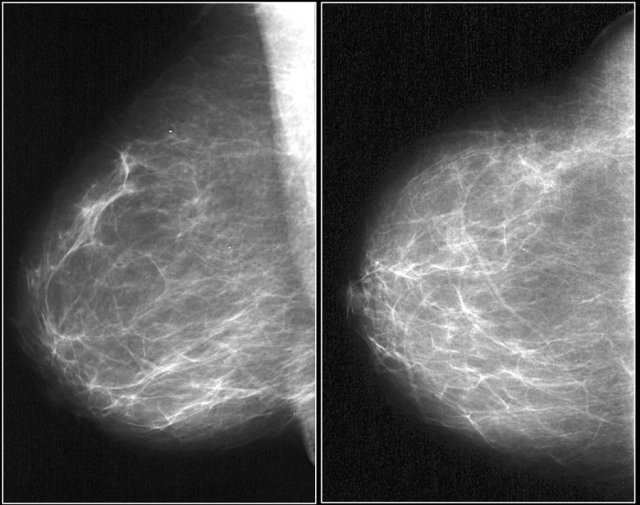

Here an example of a focal asymmetry seen on MLO and CC-view.

Local compression views and ultrasound did not show any mass.

Here an example of global asymmetry.

In this patient this is not a normal variant, since there are associated features, that indicate the possibility of malignancy like skin thickening, thickened septa and subtle nipple retraction.

Ultrasound (not shown) detected multiple small masses that proved to be adenocarcinoma.

The PET-CT shows diffuse infiltrating carcinoma.